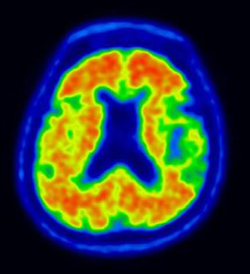

| ▲ 알츠하이머병의 가능성이 높다는 것을 의미하는 영상이다. 붉을수록 베타아밀로이드 밀도가 높다. |

기존의 PET 검사는 단면 4개를 흑백영상으로 확인했지만 이번 신의료기술은 베타아밀로이드가 가장 먼저 쌓이는 부위의 밀도를 컬러영상으로 확인하면서 베타아밀로이드의 축적을 쉽게 확인할 수 있는 것이 장점이다.